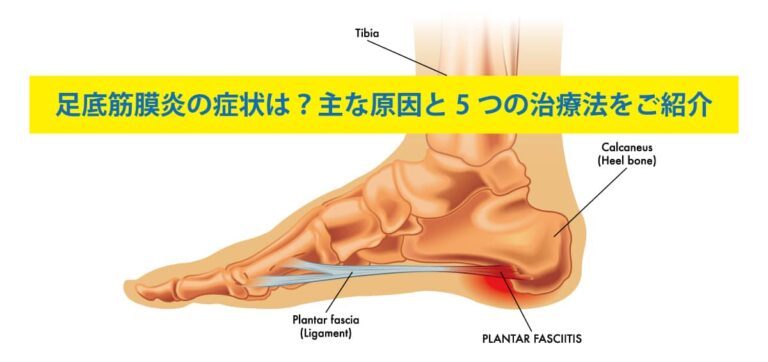

足底筋膜炎は、かかとや足の痛みの一般的な原因です。幸いなことに、自宅でできるストレッチや足のマッサージは痛みを和らげ、症状の慢性化を防ぐのに役立つ可能性があります。

「ランナー、立ち仕事が多い人、扁平足や高いアーチの人は、足底筋膜炎になりやすいです。正しい歩き方を心がけ、筋肉が硬くならないように運動やストレッチをする必要があります」と彼女はアドバイスします。

足底筋膜炎は、多くの人、特にランナーや立ち仕事が多い人にとって一般的で痛みを伴う症状です。自宅でのマッサージやストレッチは痛みを和らげ、症状の慢性化を防ぐのに役立ちます。